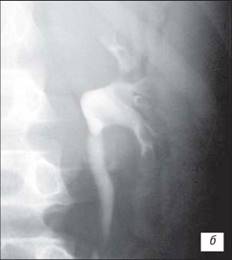

Висхідна цистографія

На даній рентгенограмі спостерігаємо активно-пасивний міхурово-сечовий рефлюкс зліва 4 ступені. Виражена дилатація чашечко-мисочкової системи, деформація чашок.

а – у фазі максимального наповнення сечового міхура, пасивний рефлекс;б – у фазі сечовипускання, активний рефлекс.